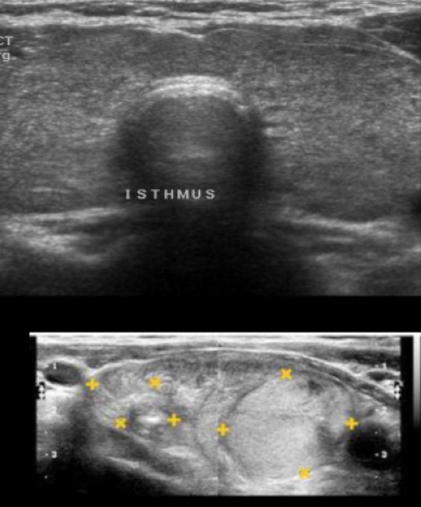

metodo ideal dx

A

US

para q se usa us

valorar el tamaño, lesiones y vascularizacion